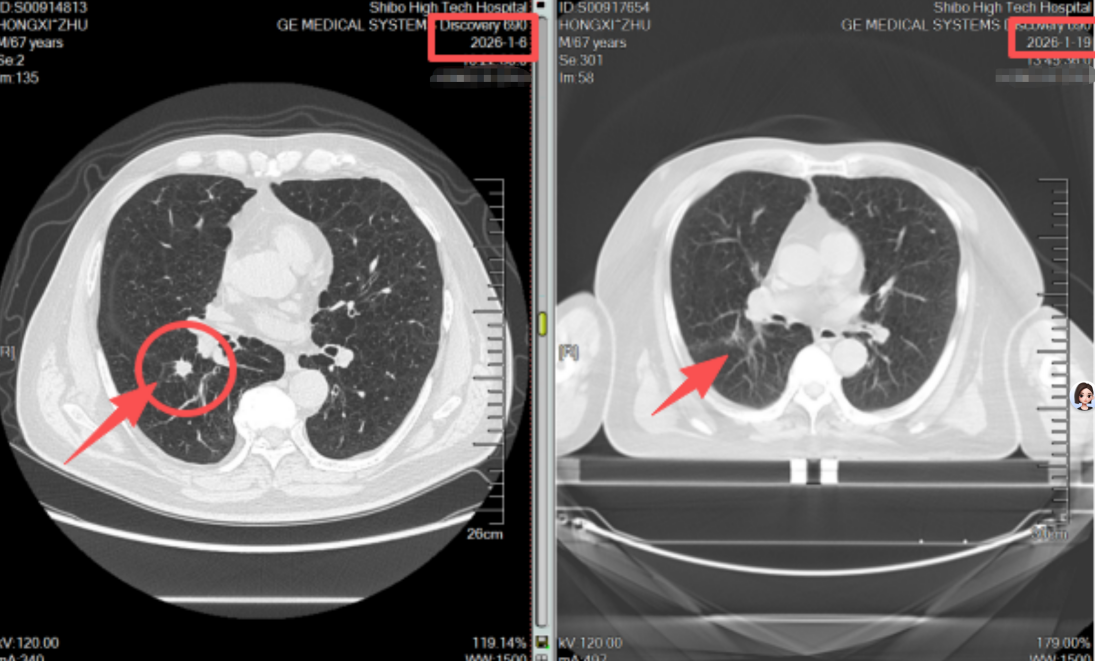

不同于传统放疗需数十次照射、持续一两个月,患者进需要数次的射波刀治疗,全程无切口、无出血、无需麻醉,每次治疗约30分钟,结束后即可自主离院。治疗两周后复查CT,影像结果令人振奋:原本的肺结节病灶基本消失,周围正常肺组织无任何损伤,患者身体状态良好,无明显不适症状。